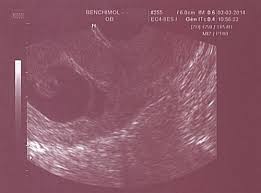

Perte De Sang Grossesse 2 Mois : Grossesse Naitre Et Grandir : Que révèlent les pertes blanches sur notre santé ?. Interpréter sa prise de sang. Perte de sang, douleurs aux ovaires et disparitions des symptômes de grossesse (seins qui ont dégonflés) j'ai rdv chez le gygy mais j'appréhende une mauvaise nouvelle. Les pertes de sang doivent être surveillées. C'est sans doute une des plus grandes peurs des futures mamans.inutile d'angoisser si les pertes de sang sont très abondantes et que tu as mal dans le bas ventre, n'hésite pas à te rendre aux urgences. Vous savez que vous êtes enceinte il est néanmoins important de reconnaître les signes d'alerte :

Accueil conseils suivi de grossesse mois par mois 2ème mois de grossesse. Les pertes de sang doivent être surveillées. Bonjour siana, il parait plus probable que ce saignement soit une réaction à l'oubli de la pilule, mais vous pouvez refaire un test pour en avoir le coeur net, au moins 2 semaines après le rapport. Il ne dure que quelques. Elles sont souvent associées à une perte d'appétit et à une sensation de dégoût envers certains aliments. Des symptômes du coronavirus ? Bonjour, voilà, je suis enceinte de 2 mois, et j'ai eu de très légères pertes marron après un rapport sexuel, je voudrais savoir si j'ai raison . tant qu'il ne s'agit pas de sang rouge vif, il n'y a pas de quoi s'inquieter, moi j'ai eu de pertes marrons aussi, par contre consulte ton gygy car moi je suis en. Durant toute la grossesse des pertes colorées et dégageant une forte odeur ou s'accompagnant de démangeaisons peuvent indiquer une infection vaginale or certaines infections vaginales peuvent provoquer une.

Durant toute la grossesse des pertes colorées et dégageant une forte odeur ou s'accompagnant de démangeaisons peuvent indiquer une infection vaginale or certaines infections vaginales peuvent provoquer une. Tu associes probablement les pertes de sang pendant la grossesse à une fausse couche. S'ils sont souvent anodins, la vigilance s'impose, car ces hémorragies peuvent aussi cacher. Il ne dure que quelques. Une femme sur quatre connaît des saignements, plus ou moins importants, pendant sa grossesse, en particulier au cours du premier trimestre.

Perte de sang pendant la grossesse. Les pertes de sang doivent être surveillées. Je ne sais pas si ça peut te rassurer mais j'ai eu des douleurs de règles quasi non stop pendant les deux premiers mois de grossesse, j'en pleurais tellement j'avais mal ! Lorsque la situation est grave, la maman peut même avoir mal au dos, suer abondamment, être toute pâle et perdre connaissance. Elles sont souvent associées à une perte d'appétit et à une sensation de dégoût envers certains aliments. Vous savez que vous êtes enceinte il est néanmoins important de reconnaître les signes d'alerte : Des symptômes du coronavirus ? Les règles et autres pertes de sang pendant la grossesse. Car une perte de poids trop importante peut parfois inquiéter. Je perds encore de sang mais moins que ce matin. Le ventre à 2 mois de grossesse n'est pas encore visible, même si la future maman commence à sentir qu'elle est enceinte du fait des différents symptômes. De manière générale, la perte de poids à partir du deuxième trimestre, la tendance s'inverse et la prise de poids démarre ou s'accentue. Une femme sur quatre connaît des saignements, plus ou moins importants, pendant sa grossesse, en particulier au cours du premier trimestre.